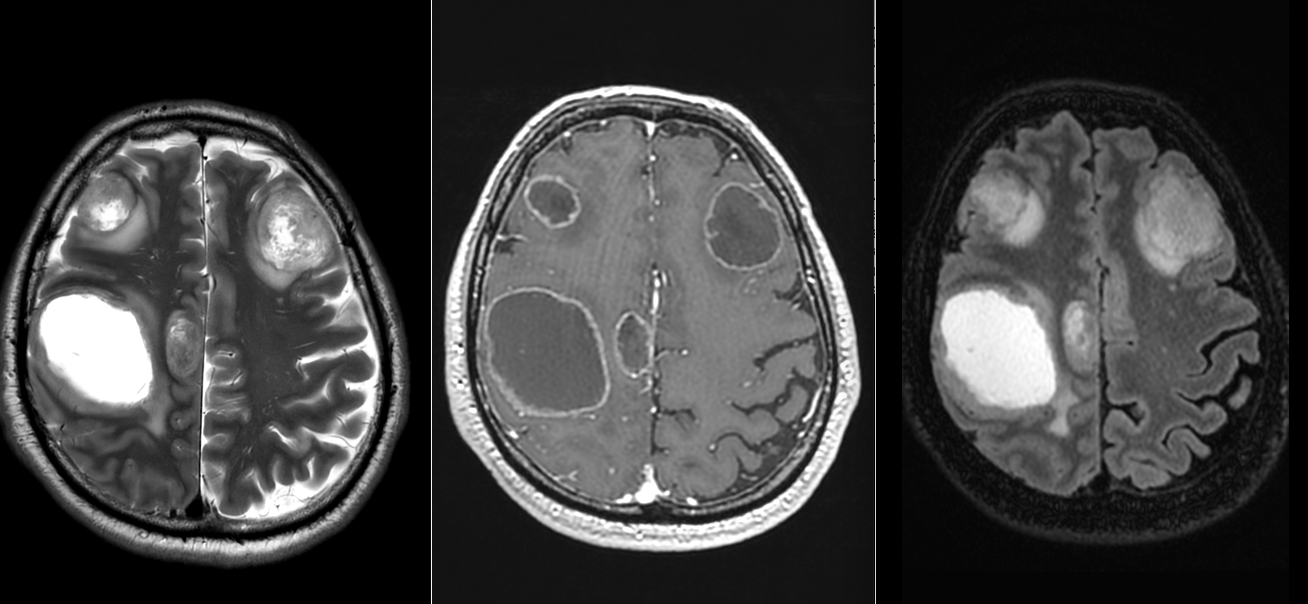

Metastazele cerebrale apar frecvent în emisferele cerebrale (80%), mai rar la nivelul cerebelului (15%) sau trunchiului cerebral (5%). Localizarea influențează simptomele și posibilitățile de tratament.

- Imagistică cerebrală: RMN-ul cu substanță de contrast este metoda de elecție, dar și CT-ul poate fi util.

Tratamentul metastazelor cerebrale este complex și personalizat în funcție de: numărul de metastaze, localizare, dimensiune, starea generală a pacientului, tipul tumorii primare și alte comorbidități.

- În mod obișnuit se operează metastaze cerebrale unice, dar în cazuri selecționate se pot aborda metastaze cerebrale multiple – chiar și 4 tumori, în același timp anestezic sau în mai multe etape.

- În mod particular metastazele chistice se pretează la intervenție chirurgicală, având un răspuns slab la radioterapie per primam.